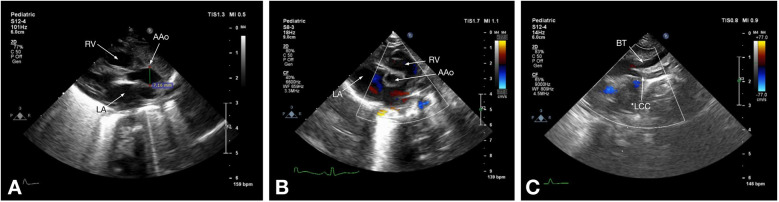

主动脉弓中断(IAA)是一种罕见的先天性心血管异常,其特征是升降主动脉之间缺乏连续性,通常伴有先天性心脏缺陷,如室间隔缺损和动脉导管未闭。准确的术前影像对手术计划和患者管理至关重要。本研究旨在比较超声心动图和计算机断层血管造影(CTA)在评估IAA患者胸部表现方面的诊断准确性。对2020年9月至2023年1月期间在哈萨克斯坦阿斯塔纳大学医学中心心脏中心诊断为IAA的58例患者(中位年龄:18天)进行了回顾性分析。常规超声心动图和多层CTA采用标准化方案。计算敏感性、特异性和其他诊断性能指标。采用McNemar和Wilcoxon有符号秩检验进行统计学比较,p p p = 0.09)。IAA主要为A型(48.3%)和B型(46.6%),34.5%的患者发现升主动脉发育不全。超声心动图仍然是IAA的一种实用的初始成像方式,具有便携性和成本效益。然而,CTA显示出优越的诊断准确性和解剖分辨率,使其成为详细的术前评估和手术计划的首选工具。未来有更大的队列和其他方式的研究可以进一步完善IAA的诊断策略。

Interrupted aortic arch (IAA) is a rare congenital cardiovascular anomaly characterized by the absence of continuity between the ascending and descending aorta, often accompanied by congenital heart defects such as ventricular septal defects and patent ductus arteriosus. Accurate preoperative imaging is essential for surgical planning and patient management. This study aimed to compare the diagnostic accuracy of echocardiography and computed tomography angiography (CTA) in evaluating thoracic findings in patients with IAA. A retrospective analysis was conducted on 58 patients (median age: 18 days) diagnosed with IAA between September 2020 and January 2023 at the Heart Center, University Medical Center, Astana, Kazakhstan. Conventional echocardiography and multislice CTA were performed using standardized protocols. Sensitivity, specificity, and other diagnostic performance metrics were calculated. Statistical comparisons were made using McNemar's and Wilcoxon signed-rank tests, with p < 0.05 considered significant. Echocardiography correctly identified 91.4% of IAA cases, while CTA achieved 100% sensitivity and specificity. McNemar's test revealed a significant difference in diagnostic performance favoring CTA (p < 0.05). Measurements of the ascending aorta diameter showed no statistically significant difference between the two modalities (p = 0.09). IAA was predominantly type A (48.3%) and type B (46.6%), with hypoplastic ascending aorta identified in 34.5% of patients. Echocardiography remains a practical initial imaging modality for IAA, offering portability and cost-effectiveness. However, CTA demonstrated superior diagnostic accuracy and anatomical resolution, making it the preferred tool for detailed preoperative evaluation and surgical planning. Future studies with larger cohorts and additional modalities could further refine diagnostic strategies for IAA.